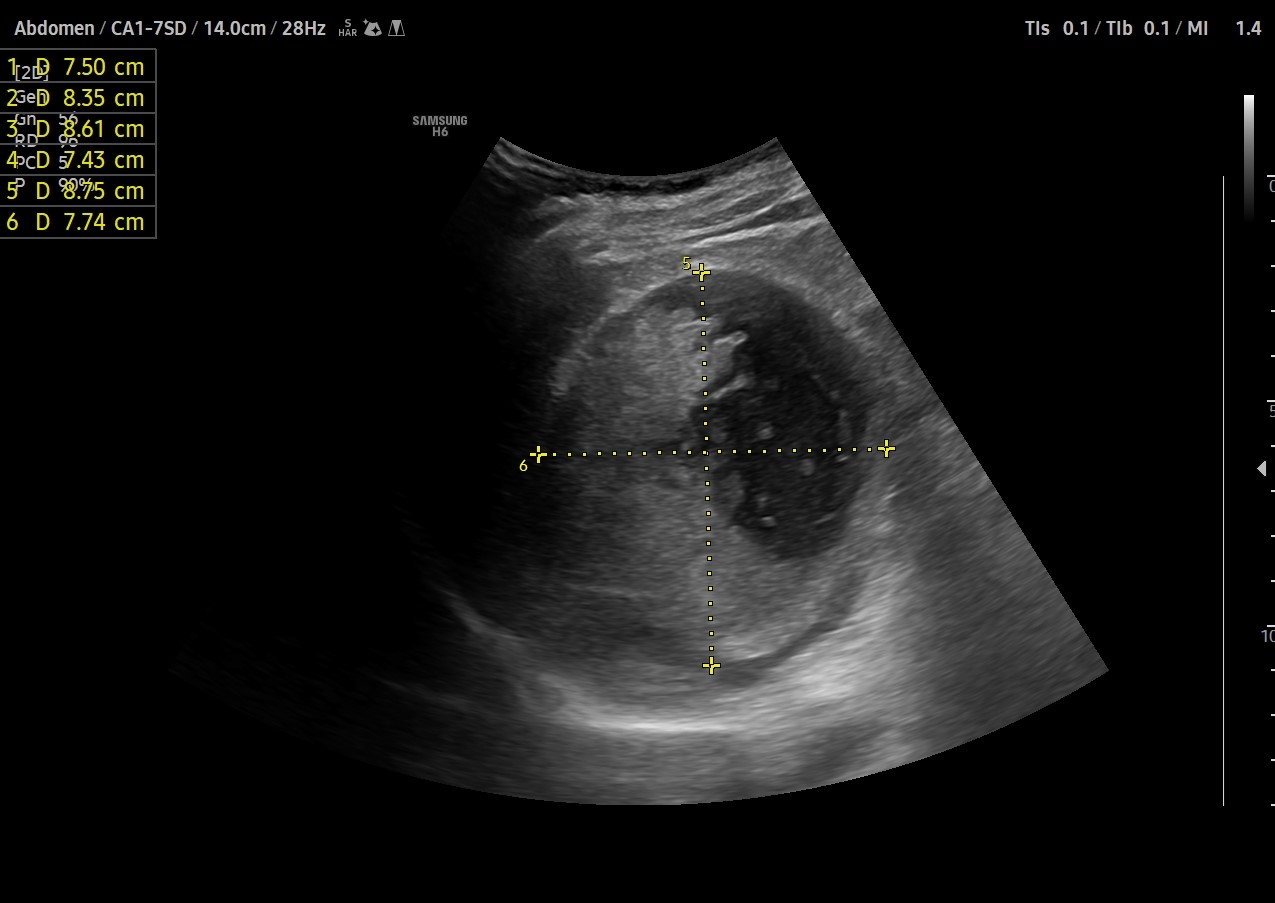

Dada la clínica y la afectacion del estado general se realiza ecografía clínica.

Hallazgos ecográficos

Se objetiva en HI masa bien delimitada de aprox. 8x8cm,que no parece tener relación con riñón izquierdo ni con el bazo,situado entre ambas estructuras,visible también a nivel de mesogastrio, de caracteristicas sólido-quísticas, inmóvil, sin captación de Doppler.